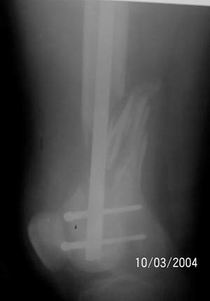

A 34 year old male was injured in a car accident.

The femur injury was treated by long retrograde interlocking nail.

It was used ORTHFIX Retrograde nailing System, diameter 11.